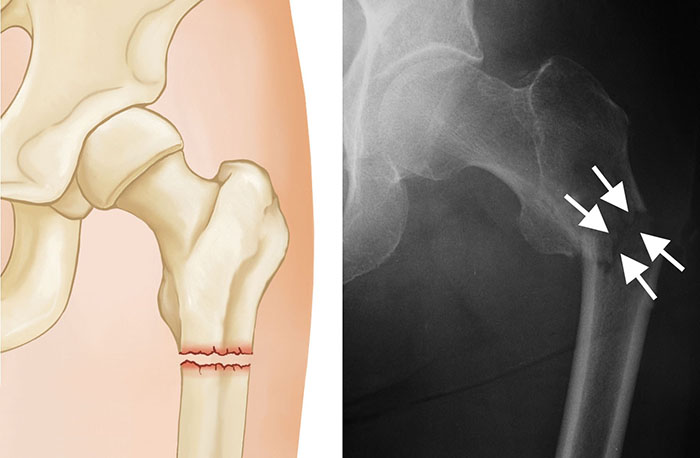

Subtrochanteric Fracture

Subtrochanteric fractures involve the upper part of the shaft of the femur, just below the hip joint.

They are treated surgically with an intramedullary nail into the shaft of the femur and a screw placed through the nail into the femoral head.

To keep the bones from rotating around the nail or from shortening (telescoping) on the nail, additional screws may be placed at the lower end of the nail near the knee. These are called interlocking screws.

In some cases, your surgeon may choose to use a compression screw with a long side plate instead of a nail.

treatment options for subtrochanteric fracture

X-rays show treatment options for a subtrochanteric fracture: (Left) Intramedullary nail and screw, (Center) An interlocking screw has been placed at the lower end of the femur to prevent the bone from shortening. (Right) Side plate and compression screws.